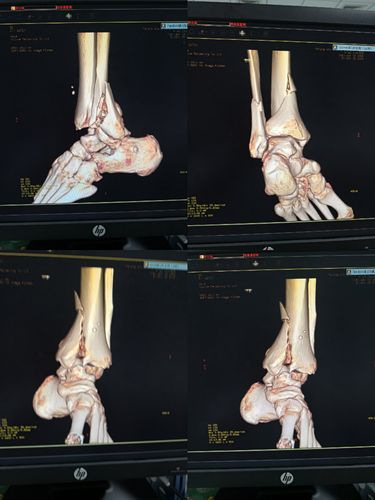

甘肃省人民医院骨一科杨青山副主任医师团队:踝关节骨折

左踝关节骨折

胫骨远端骨折

Pilon骨折